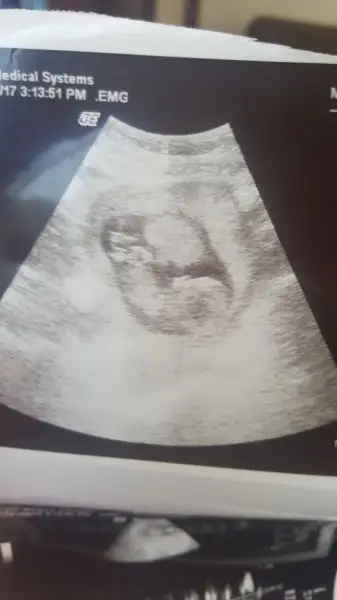

Hanımlar bişey sorcam, bugün kontrole gittim doktor bebek iyi sorun yok dedi, ayakta fazla kalmıyorsundur heralde dedi ben biraz huylandım öyle sorunca. Eve gelince de ultrason görüntülerinde bebeğin üstünde bişey olduğunu farkettim böyle bişey gören var mı ultrasonda? Moralim bozuldu :/

Hanımlar bişey sorcam, bugün kontrole gittim doktor bebek iyi sorun yok dedi, ayakta fazla kalmıyorsundur heralde dedi ben biraz huylandım öyle sorunca. Eve gelince de ultrason görüntülerinde bebeğin üstünde bişey olduğunu farkettim böyle bişey gören var mı ultrasonda? Moralim bozuldu :/Eki Görüntüle 2003183 Eki Görüntüle 2003184

Canım sanki plesentaya benziyor o bebeğin üstündeki şey yani bebeğin eşi. Normalde ultrason fotoğrafında görünür mu bilmem ama doktorlar ultrasonda gördüklerine göre fotoğrafta da görülebilir demekki. Koru bişey olsa doktorlar kesinlikle gizlemiyorlar bu konuda. Ayrıca ayakta kalma demesinin bununla bir ilgisi yok ben de öğretmenim doktorum Fazla Ayakta kalıyorsun tedbir amaçlı progeston verebilirim demişti ben onun yerine rapor aldım 10 gün şimdi yine işe başladım ama genelde oturuyorum fazla dolanmiyorum. Çok ayakta durmanın riskleri var o yüzden doktorun sana uyarı anlamında demistir

Ne bileyim doktor acaba gözden mi kaçırdı diye korktum. İnternette de bu haftanın ultrason görüntülerine baktım hiçbirinde böyle bişey yok. Plasenta mı ayrıldı acaba diye korkuyorum

Yok canım plesenta ayrılmış olsa bunu gözden kaçırmasi mümkün değil doktorum ki ben o olayın son haftalarda olduğunu duymuştum allah korusun hiç bir zaman olmasın inşallah. Bence fotoğrafın açısından dolayı plesenta çok net çıkmış. Çünkü ben daha önceden ultrason fotoğraflarına bakarken internetten hep böyle görüyordum ok işaretiyle de plesenta yazıyordu üstünde hep